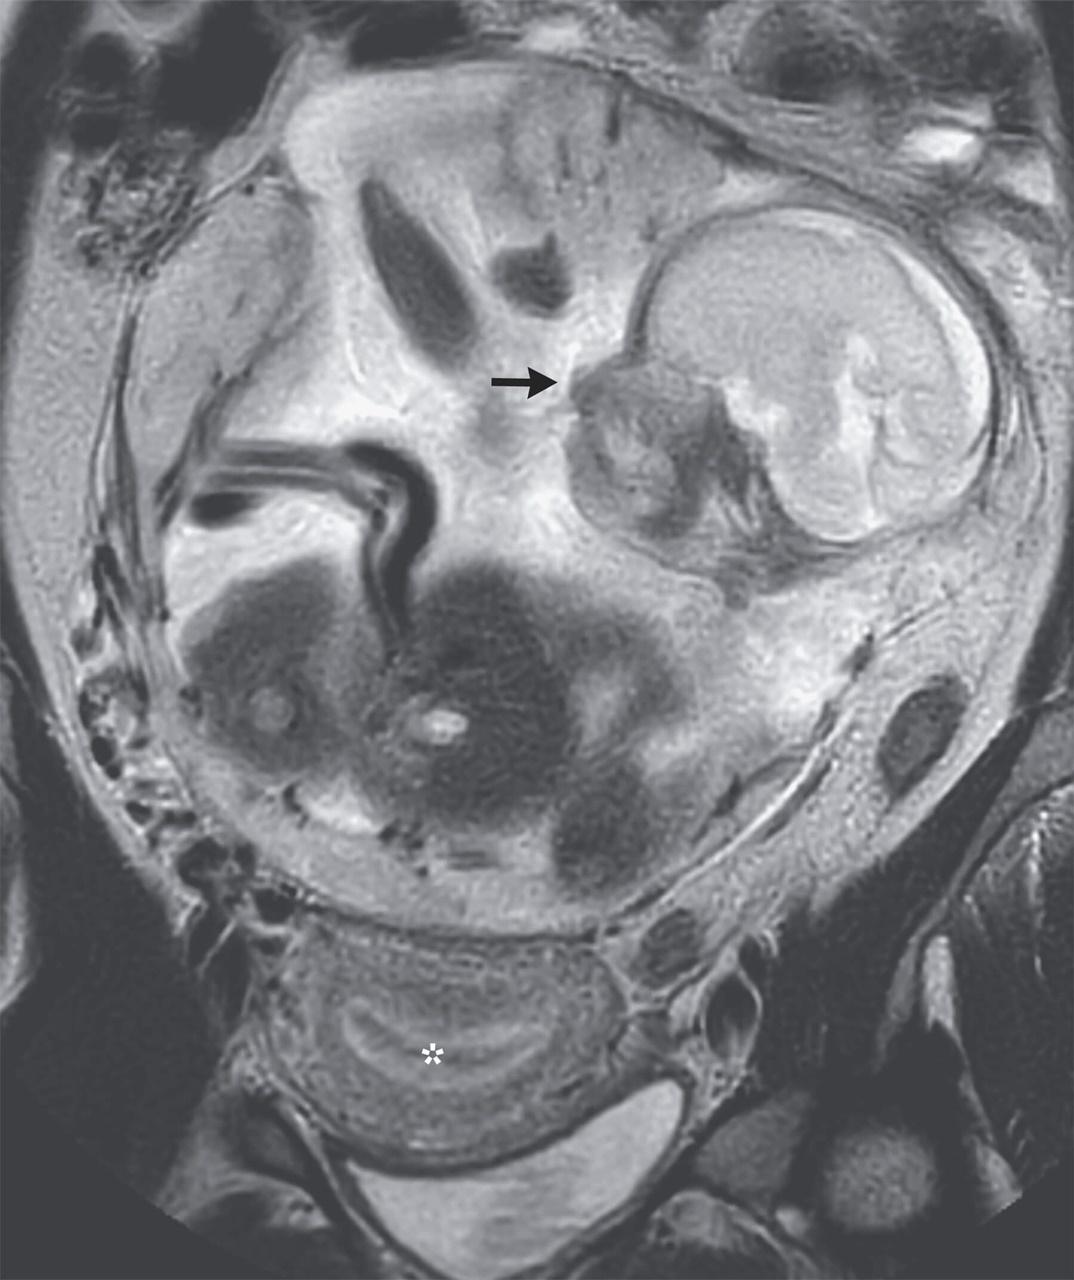

法女胃痛10日闖ER求醫,驚揭胎兒生長於腸道。(網上圖片)

有關病例已發表於《新英格蘭醫學雜誌》(The New England Journal of Medicine),文章指出,該名法屬非洲印度洋島嶼Réunion婦女,在經過10天嚴重「胃痛」後前往急症室求醫,被發現在胃部與腸道之間子宮外孕,且胎兒奇跡般存活並發展到6個月大。

胎兒在胃部與腸道之間子宮外孕,且奇跡地存活並成長至6個月大。(網上圖片)

報告指出,雖然受精卵從輸卵管到子宮腔著床過程中,有可能因輸卵管破裂「逃離」子宮腔,但機率僅3萬分之1且「失去胚胎機率高達90%」,胚胎即使倖存也有「5分之1機率腦損傷或有先天缺陷」。院方為慎重起見,將女子轉送法國當地治療,醫院的團隊醫生判斷胎兒在8個月大手術,胎兒存活機率可達80到90%屬最高,建議女子等待5個星期以進行剖腹生產。

團隊先是成功把胎兒從腸胃之間取出,送往新生兒加護病房觀察,再於剖腹產2個星期後對女子進行腹腔胎盤清除手術。目前女子及嬰兒已出院,返回Réunion島上的家人團聚。